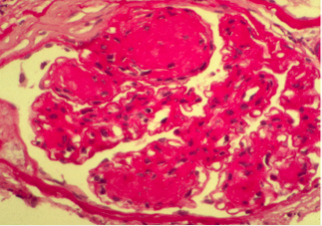

Diabetic GN H&E

• Thickened GBM

• Nodular pattern of mesangial scloerosis and thickened BM

• Glomerular hypertrophy => podocyte loss